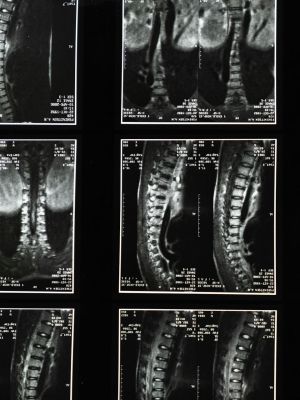

MSCT snimanje kičmeMSCT snimanje kičme

Promene koje se mogu uočiti na MSCT snimcima kičme

Multislajsni CT kičme omogućava lekarima da jasno sagledaju promene koje mogu biti uzrok tegoba ili ograničenja u pokretu.